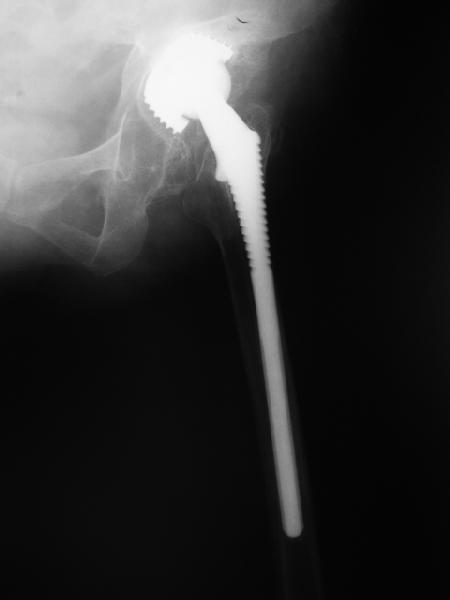

24 апреля 2005 г. правый сустав фас (тут и болит)

С выбором имплантата можно не согласиться, но скорее всего просто поставили то, что было в наличии. :( Вертлужный компонент установлен

слишком медиально. По представленным рентгенограммам нельзя исключить нарушение целостности дна вертлужной впадины. Даже если в данным момент нестабильности нет, то она обязательно возникнет и скорее всего, создаст

На представленных Р-граммах явных признаков нестабильности эндопротеза нет. Чашка хоть и медиализирована, но стоит так же, как и 3 года назад и остеолиза нет. Есть остеолиз вокруг проксималного отдела ножки, но линия тонкая и не захватывает дистальный отдел. Судя по клинике, можно думать о травме (отрыв) ягодичных мышц в